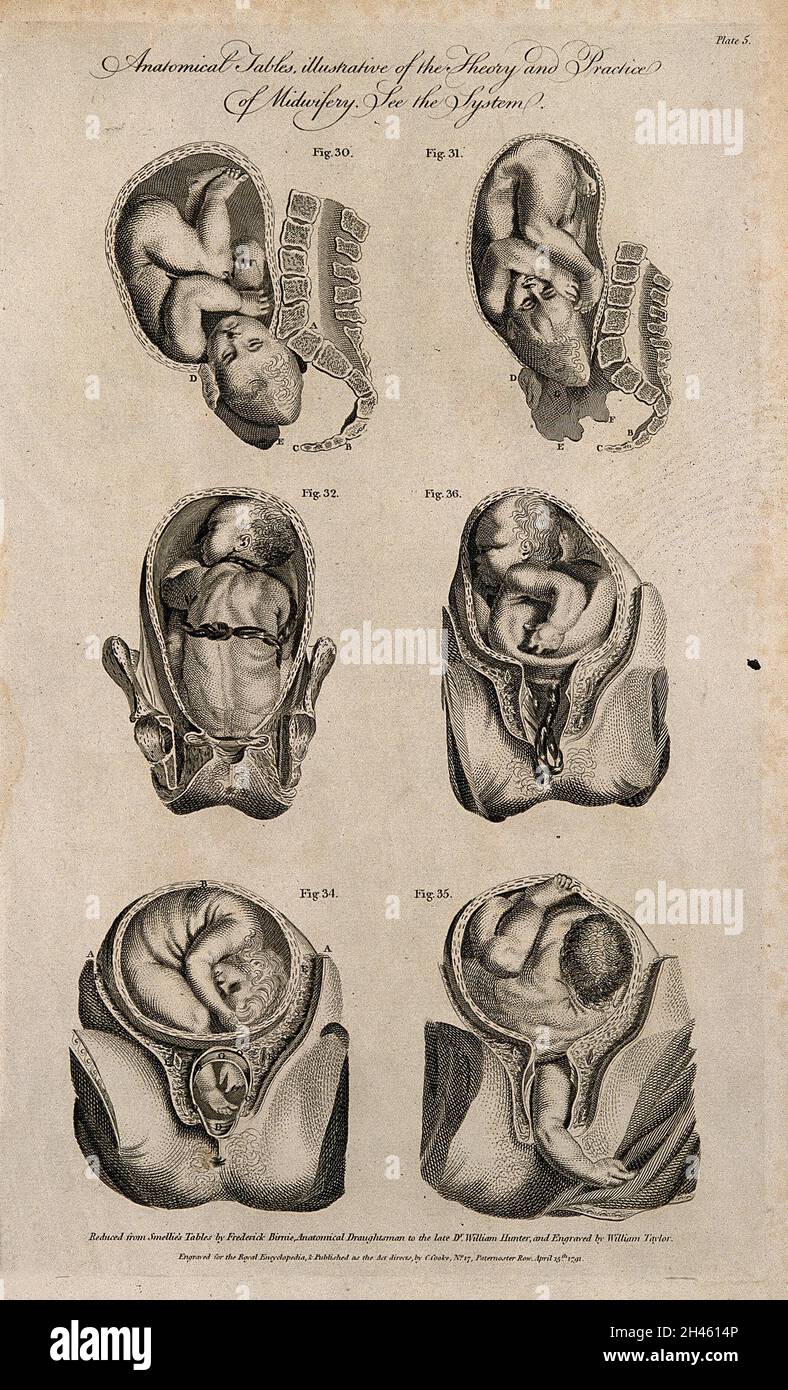

Eight diagrams illustrating babies in the womb in different positions about to enter the world. Etching by Barlow. Stock Photohttps://www.alamy.com/image-license-details/?v=1https://www.alamy.com/eight-diagrams-illustrating-babies-in-the-womb-in-different-positions-about-to-enter-the-world-etching-by-barlow-image449997775.html

Eight diagrams illustrating babies in the womb in different positions about to enter the world. Etching by Barlow. Stock Photohttps://www.alamy.com/image-license-details/?v=1https://www.alamy.com/eight-diagrams-illustrating-babies-in-the-womb-in-different-positions-about-to-enter-the-world-etching-by-barlow-image449997775.htmlRM2H434N3–Eight diagrams illustrating babies in the womb in different positions about to enter the world. Etching by Barlow.